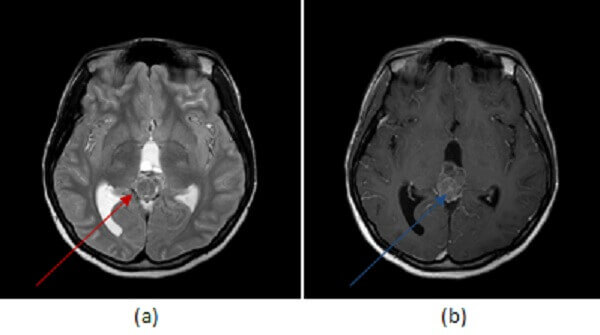

Figure 1: axial T2 (a, red arrow) and FLAIR (b, blue arrow) sequences demonstrate a large lobulated pineal mass with ill defined borders and heterogenous signal. (c, green arrow) post contrast T1 demonstrates heterogenous enhancement to the mass. There is hydrocephalus, manifested by an enlarged third ventricle (purple arrow).

Pineoblastomas are highly malignant tumors of early childhood, more common in females with peak incidence of 3 years of age. Pineoblastomas are typically large, solid, lobulated masses that compress or infiltrate adjacent structures, that seed the meninges and that may have drop metastasize in the spine. They are heterogenous masses, hyperdense on CT and iso/hypo dense on T2. They enhance heterogeneously and demonstrate restricted diffusion due to high tumor cellularity. Treatment includes surgical resection and radiation of the entire neuraxias (due to the high frequency of metasatasis at presentation).